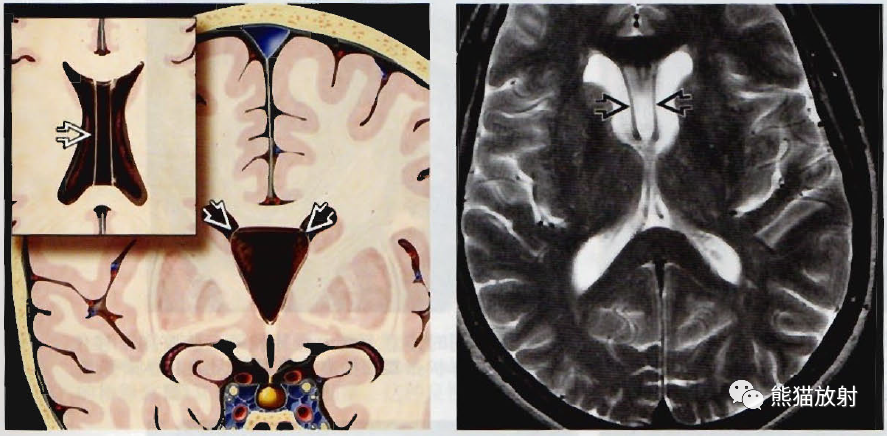

(左) 冠位图和轴位插图显示透明隔腔和韦尔加腔的典型表现。注意双侧侧脑室间的指状脑脊液积聚。

(右) 轴位T2WI显示透明隔腔为透明隔两分叶之间的脑脊液积聚。